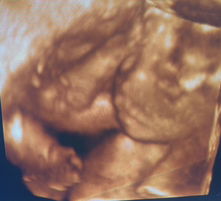

Okay lang po ba nakatagilid matulog si LO ko? 1 month pa lang po sya. Nagagalit sya kapag ihinihiga